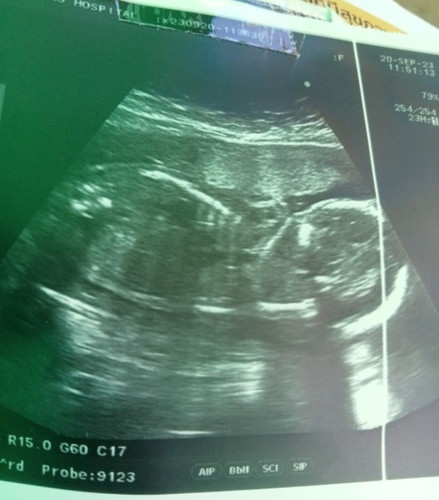

อายุแม่ กี่วีคกันแล้วค่ะ ของแม่ 27 วีค 810 กรัม น้อยไปไหมค่ะ

แนะนำอาหารบำรุงตัวเล็กหน่อยค่ะ